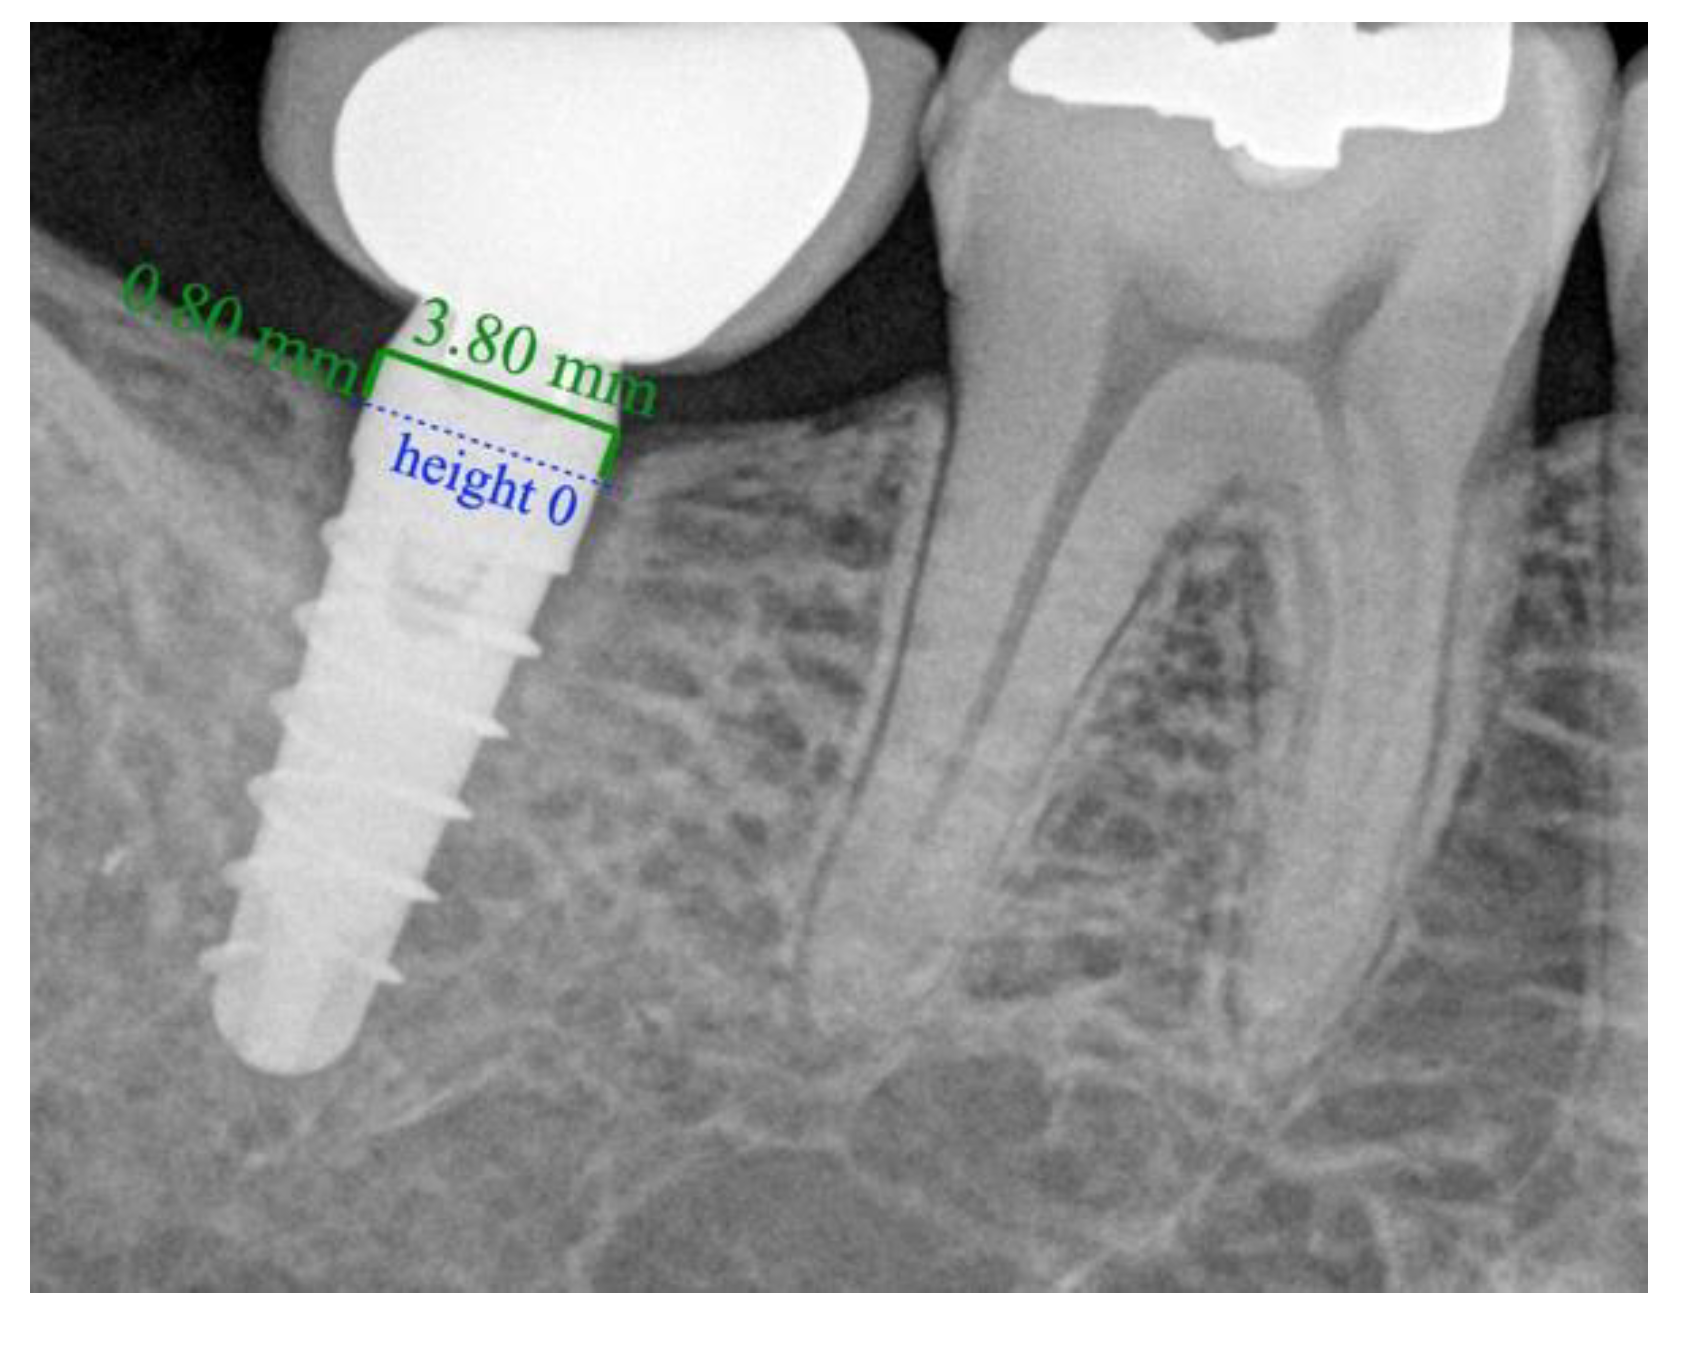

2.3. Radiographic Technique and Bone Loss Measurement Method